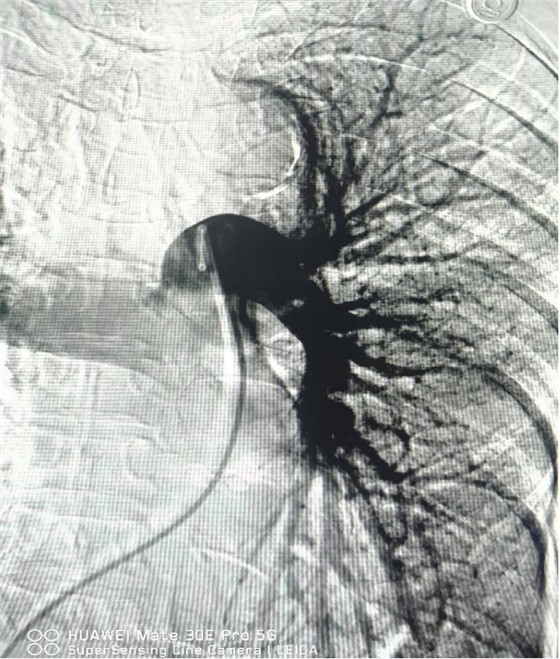

術(shù)后肺動脈血流恢復通暢

經(jīng)綜合評估并與家屬充分溝通后,局麻下行肺動脈造影,提示左肺動脈主干及左肺下葉動脈閉塞,立即予以經(jīng)皮肺動脈栓塞導管介入碎栓溶栓術(shù)。在心內(nèi)科韋鋒主任、郭良玉主治醫(yī)師及成婷護師的默契配合下,爭分奪秒順利完成手術(shù)。術(shù)后即刻復查肺動脈造影示左肺動脈主干及左肺下葉動脈恢復血流,生命體征穩(wěn)定,指脈氧恢復至100%。經(jīng)過精心治療與護理,目前患者已康復出院。